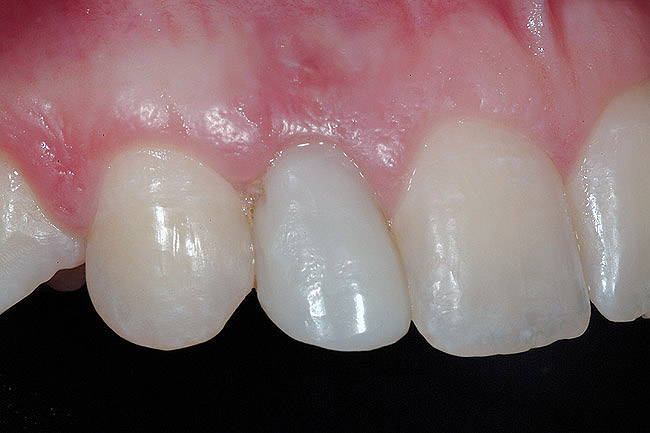

The 3-month postoperative views can be seen in Figure 18 through Figure 20. Note the excellent soft tissue emergence profiles obtained from the properly contoured provisional restorations. After removal of the provisional restorations, further inspection of the contoured emergence profile obtained has been accomplished (Figure 21 and Figure 22). Before impression techniques, transfer copings were seated over the abutment portion of the one-piece implant (Figure 23). A full-arch impression was then taken using medium-body impression material (Take 1 Advanced, Kerr Corporation, Orange, CA) and a regular-body wash material (Take 1 Advanced) to pick up the detail of the emergence profile and impression coping (Figure 24 through Figure 26). After allowing the impression material to set, the impression is then removed from the mouth and inspected (Figure 27). The Take 1 Advanced Medium body has a more rigid set than most other medium materials, so when the coping is placed back in the impression, the possibility of movement during casting is reduced. Please note how the emergence profile obtained has been registered in the impression, and can easily be transferred to the laboratory technician. Laboratory analogues are then placed into the impression coping and forwarded to the laboratory technician for pouring of the casts and final fabrication of the esthetic implant restorations (Figure 28).

Figure 18  3-month postoperative clinical view.

Figure 19  3-month postoperative clinical view, right lateral incisor.

Figure 20  3-month postoperative clinical view, left lateral incisor.

Figure 21  Tissue emergence profiles, right lateral incisor.

Figure 22  Tissue emergence profiles, left lateral incisor.